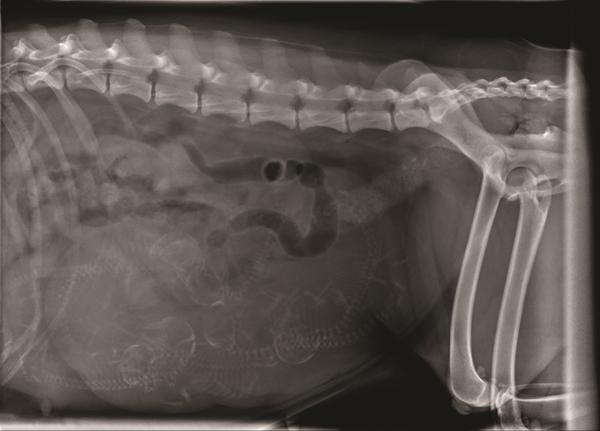

De første ser ud til at vende med bagenden først. Det kan give lidt startproblemer ved nogle tæver.

De tre ligger bare og klumper oveni hinanden.

Det bliver spændende med hvalpene. Vær forberedt på at de første kommer baglæns, og at du måske skal ind og have fat omkring hofterne på dem, for at hjælpe til lige så forsigtigt